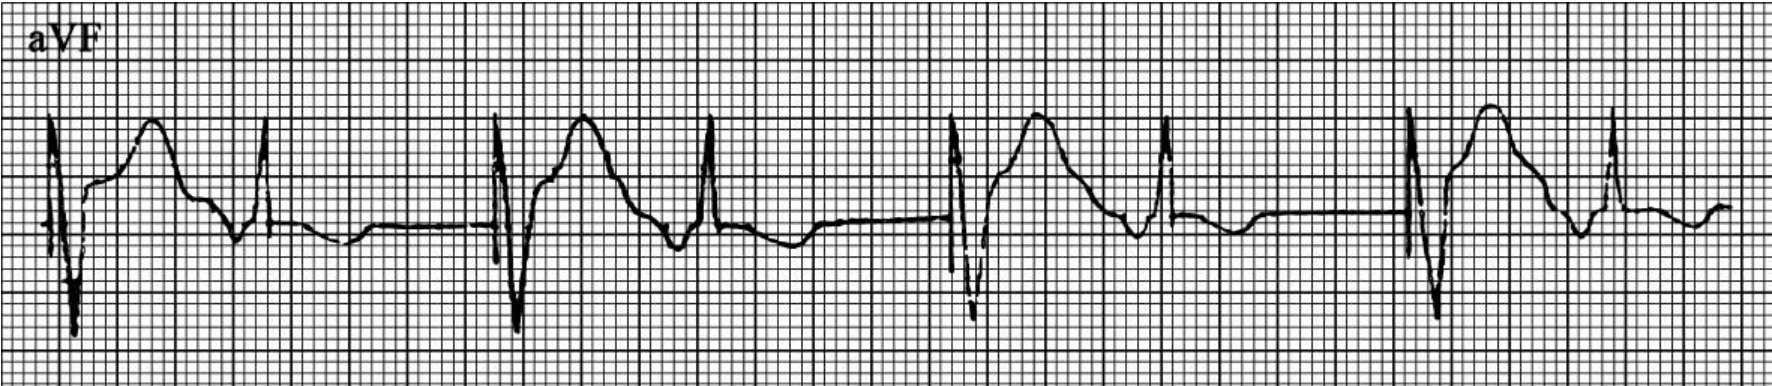

起搏器介导性心动过速的心电图特征(图61-138~140):①突然发生快速、整齐的心室起搏QRS-T波群,起搏频率低于或等于起搏器上限频率(心室最大跟踪频率),常在90~130次/min。②该快速、整齐的心室起搏QRS-T波群可能由房性期前收缩、室性期前收缩、肌电干扰等因素诱发。③快速、整齐的心室起搏QRS-T波群可突然停止,恢复双腔起搏心电图。④逆行P波常落入心室起搏的T波中而被掩盖,若能分辨出逆行P波,则P-R间期等于程控的A-V间期或R-P间期与P-R间期之和接近起搏器上限频率的R-R间期,R-P间期固定。

图61-139 室性期前收缩诱发PMT室性期前收缩经房室结逆传心房,逆传的P'波落入心室后心房不应期(PVARP)之后,心房激动被感知,形成PMT

图61-140 房颤时DDD起搏器室介入性心动过速

DDD起搏器,程控最大心室跟踪频率100次/min,图示心房纤颤时,心房感知后以VAT方式快速心室起搏形成PMT